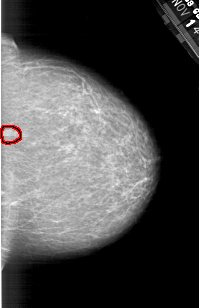

A_1321_1.LEFT_MLO

LEFT_MLO LINES 5971 PIXELS_PER_LINE 3496 BITS_PER_PIXEL 12 RESOLUTION 43.5 NON_OVERLAY

FILE: A_1321_1.RIGHT_MLO.OVERLAY

TOTAL_ABNORMALITIES 1

ABNORMALITY 1

LESION_TYPE MASS SHAPE OVAL MARGINS CIRCUMSCRIBED

ASSESSMENT 4

SUBTLETY 3

PATHOLOGY BENIGN

TOTAL_OUTLINES 1

BOUNDARY